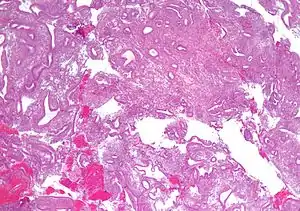

- Figure- available via license: Creative Commons Attribution 2.0 Generic - Rao, Shalinee; Sundaram, Sandhya; Narasimhan, Raghavan (2009). "Biological behavior of preneoplastic conditions of the endometrium: A retrospective 16-year study in south India". Indian Journal of Medical and Paediatric Oncology. 30 (4): 131–135. doi:10.4103/0971-5851.65335. ISSN 0971-5851. PMC 2930300. PMID 20838554.

- Figure- available via license: Creative Commons Attribution 2.0 Generic - Cote, Richard; Suster, Saul; Weiss, Lawrence; et al., eds. (2002). Modern Surgical Pathology (2 Volume Set). London: W B Saunders. ISBN 0-7216-7253-1.